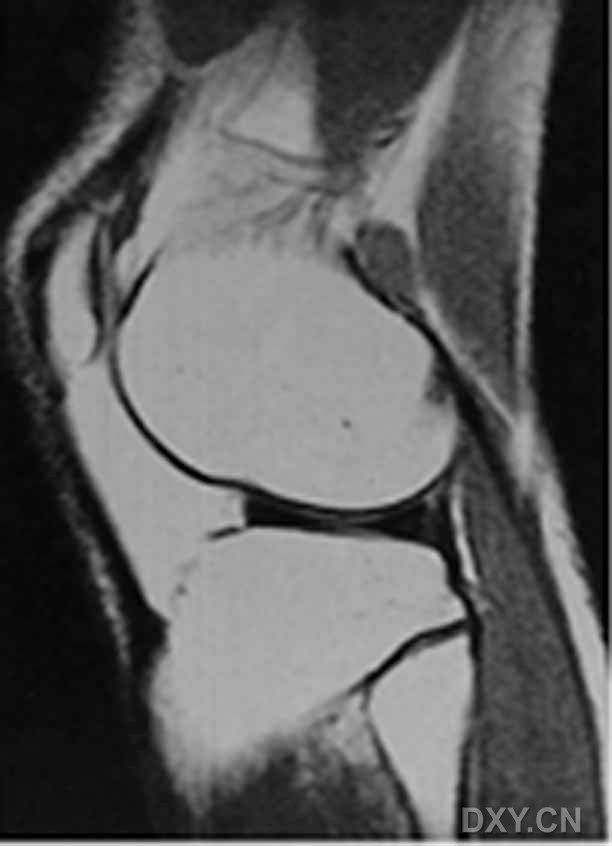

| 0级 外侧半月板表现为均匀低信号,形态规则